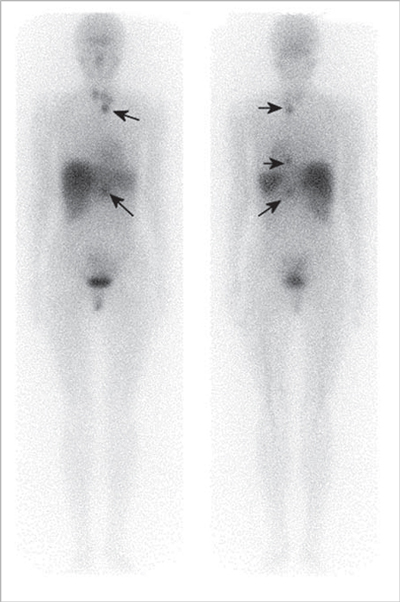

Tumor mesenquimal fosfatúrico

La osteomalacia oncogénica es un síndrome paraneoplásico caracterizado por dolor óseo y muscular, pérdida de densidad mineral ósea, marcada disminución del nivel plasmático de 1,25 dihidroxicolecalciferol, hipofosfatemia e hiperfosfaturia (Figura 13). La causa puede ser un tumor mesenquimal oculto que secreta una hormona llamada factor de crecimiento fibroblástico-23 (FGF-23), que pertenece a una clase de factores u hormonas conocidos como fosfatoninas41,42. Puede darse también en asociación con otras enfermedades tales como: cáncer de próstata, cáncer de células pequeñas, neurofibromatosis, cánceres hematológicos, síndrome del nevus epidérmico y displasia fibrosa poliostótica. El tumor mesenquimal, desde el punto de vista histológico, puede ser parecido a un variado número de neoplasias muchas de ellas benignas (hemangiopericitomas, hemangiomas, sarcomas, fibromas osificantes, granulomas, tumores de células gigantes y osteoblastomas)43. La resección quirúrgica del tumor es generalmente curativa. Sin embargo, muchos de estos tumores son pequeños y de ubicación inusual por lo que su localización suele ser muy difícil. Pueden aparecer en huesos o tejidos blandos, en cualquier parte del cuerpo. PET/CT con F18-FDG es el método más sensible para su localización, sin embargo, de baja especificidad debido a la captación de F18FDG por lesiones no neoplásicas tales como reparación de fracturas óseas, que son muy frecuentes en estos pacientes. Debido a que numerosos tumores mesenquimales expresan receptores de somatostatina, tales como tumores óseos, vasculares y perivasculares (osteosarcomas, tumor de células gigantes, angiosarcomas, hemangiopericitomas), sarcomas sinoviales, histiocitomas y tumores de origen muscular (leiomiomas, leiomiosarcomas y rabdomiosarcomas)44, el uso de trazadores para receptores de somatostatina es útil en estos pacientes. Tanto el SPECT con In111-pentatreotide como el PET con Ga68-DOTATATE u otros análogos han sido usados exitosamente para localizar estos tumores (Figura 14). La adición de imágenes estructurales (SPECT/CT y PET/CT) mejoran aún más el rendimiento del examen. Particularmente en estos casos es necesario realizar un examen de cuerpo total, desde el vértex craneal hasta los pies, incluyendo las extremidades superiores completas, debido a que el tumor puede estar en cualquier parte. Por el momento no hay estudios que comparen el rendimiento del In111-Octreoscan con PET con Ga68-octreotide.